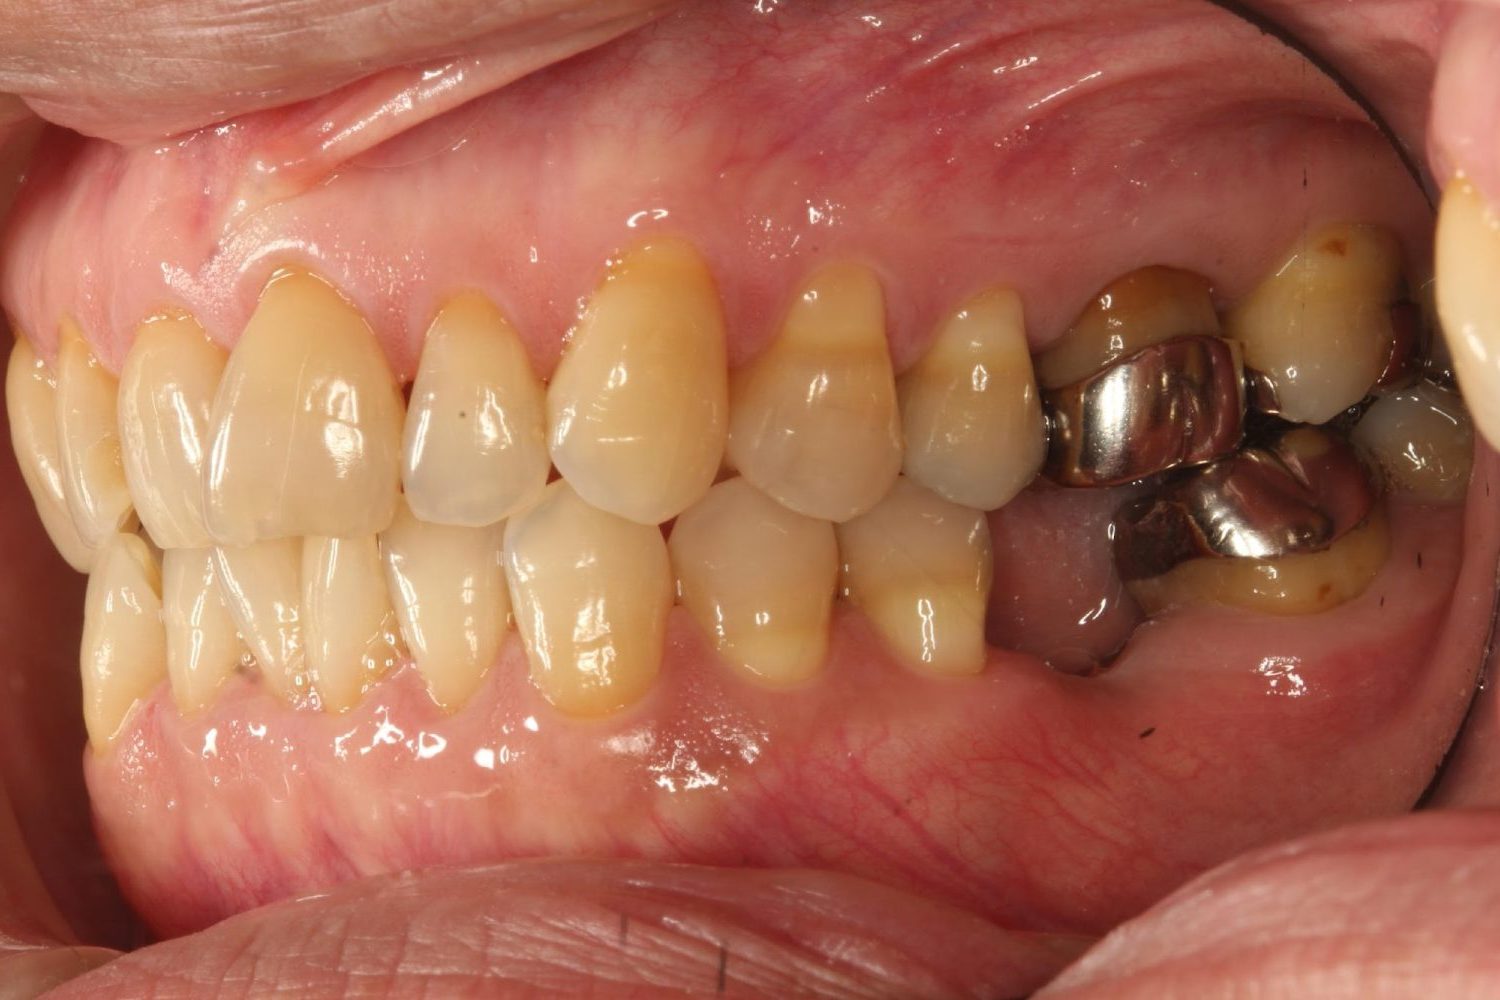

インプラント治療の症例紹介④

Before

After

主訴

義歯による疼痛

治療内容

下顎舌側に骨隆起があり義歯困難な状態。保存不可能な歯の抜歯を行い、インプラントを埋入し咬合再構成を行った。

治療費

2,851,200円(税込)

治療期間

29ヶ月

通院回数

26回

想定されたリスク

※咬合力の強い方なので、予防的にマウスピースの装着が必要。インプラント周囲炎の恐れがありました。

濱 仁隆先生

浜歯科

歯の欠損の対合歯の挺出等を修正し咬合平面を揃え咬合再構成を行った症例。